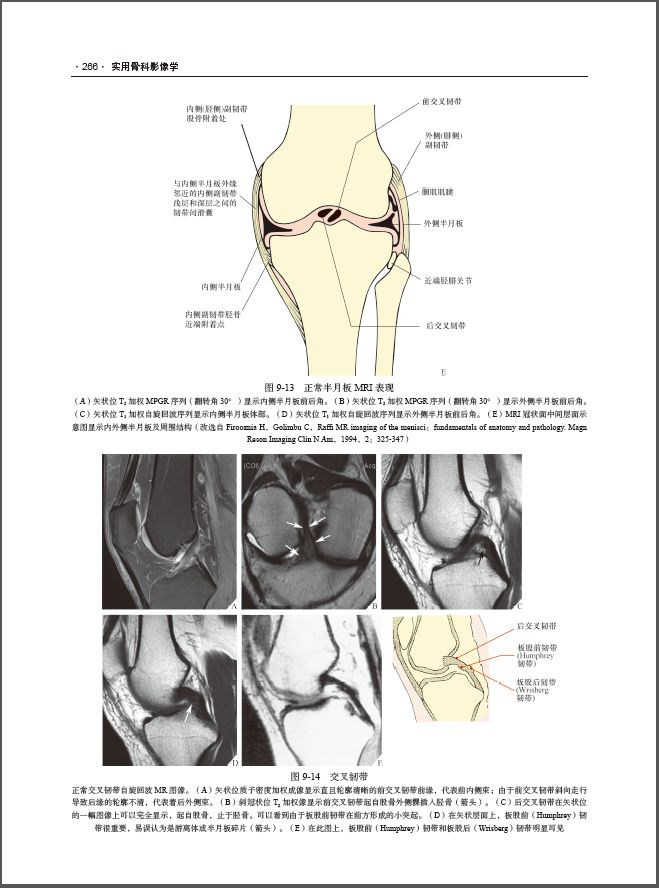

内容全面,大量高质量图片:共7篇33章,既有基础理论的论述,又有大量的高质量影像图和归纳总结便于对比的表格。

涵盖肌骨系统影像学的广泛领域 :介绍了各种设备的临床应用,包括关节造影、穿刺活检和创伤、运动医学、关节炎、肿瘤、感染及发育异常等的影像学特征、诊断和鉴别诊断。